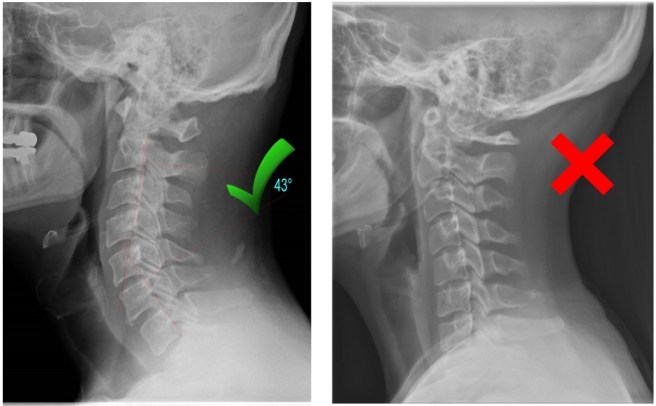

Turns out my neck is in a bit of a fix. It should have a nice curve but it’s kind of kinky. I refused to take prednisone so I’m just having four weeks of therapy and then reassessment.